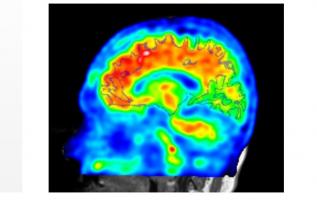

Trouble panique, trouble d'anxiété sociale et phobies, tous ces troubles anxieux partagent un facteur commun, suggère cette étude de l’Université de l'Illinois à Chicago. Cette conclusion simple et logique, documentée dans le Journal of Abnormal Psychology pourrait contribuer à mieux prendre en charge ces troubles en commençant par cibler « leur neurobiologie commune ».

Le concept d'anxiété anticipatoire : les auteurs définissent ici l'inconnu comme une menace incertaine, imprévisible dans son incidence, son intensité, sa fréquence ou sa durée et cet inconnu entraine, chez certaines personnes, un sentiment généralisé d'appréhension et d'hypervigilance et une conduite d'évitement. Le trouble ou les attaques de panique, qui entraînent une anxiété chronique ou aiguë, sont un des troubles anxieux pouvant se développer en cas de peur de l'inconnu. Cependant, de précédentes études de la même équipe suggèrent que cette sensibilité exacerbée à la menace peut être un facteur majeur et caractéristique de plusieurs psychopathologies.

Des réponses plus fortes aux chocs imprévisibles : 2 études ont été menées avec 160 participants âgés de 18 à 65 ans, dont 25 participants avec trouble dépressif majeur, 29 avec trouble anxieux généralisé, 41 avec un trouble d'anxiété sociale et 24 avec phobie spécifique, vs 41 témoins exempts de psychopathologie. Les chercheurs ont mesuré les réponses « réflexes » oculaires des participants à des micro chocs électriques, prévisibles et imprévisibles, au poignet. Les chercheurs ont mesuré la force des clignements en utilisant une électrode sous les yeux des participants. Ils ont comparé la force des clignotements en réponse aux chocs prévisibles et imprévisibles. L'expérience montre que les participants avec trouble d'anxiété sociale ou une phobie spécifique clignotent beaucoup plus fortement lors des chocs imprévisibles, par rapport aux participants sans diagnostic de trouble mental ou aux participants avec trouble dépressif majeur ou trouble d'anxiété généralisée.